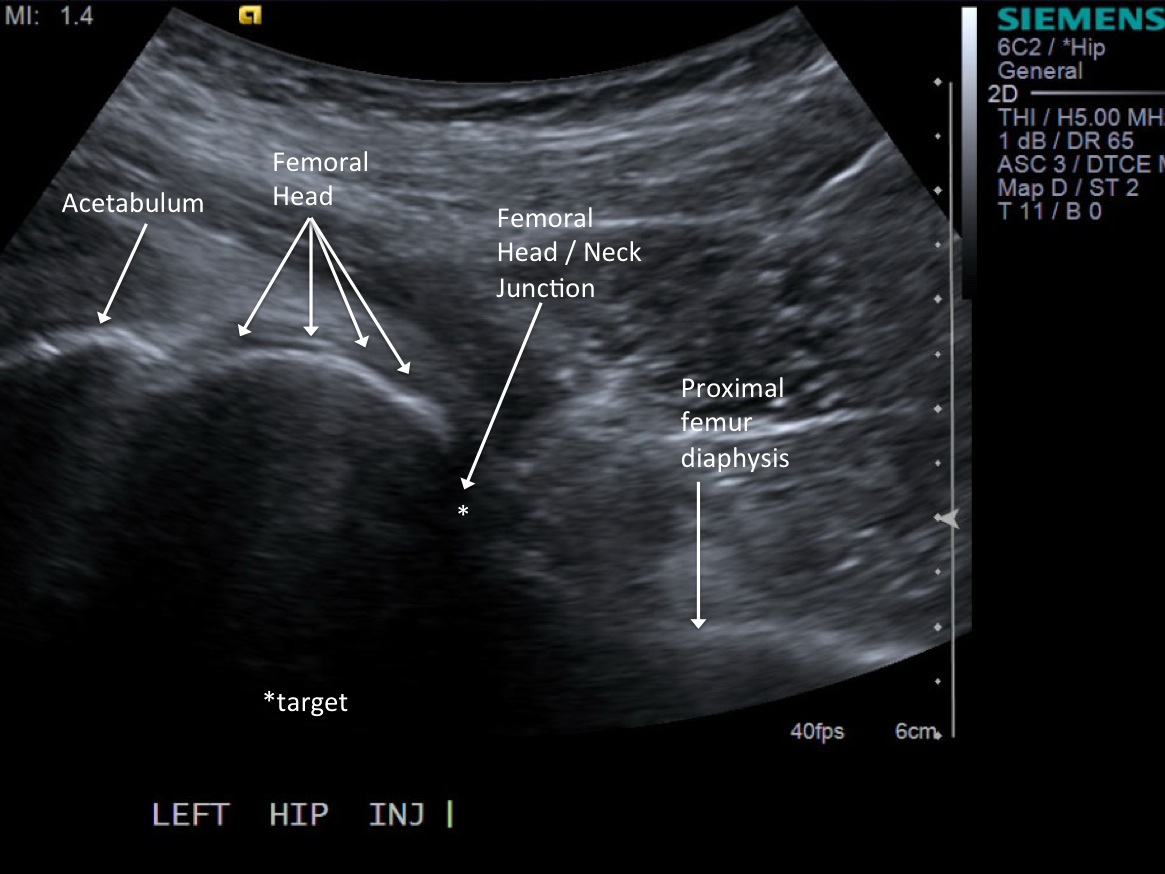

From mskultrasound.net